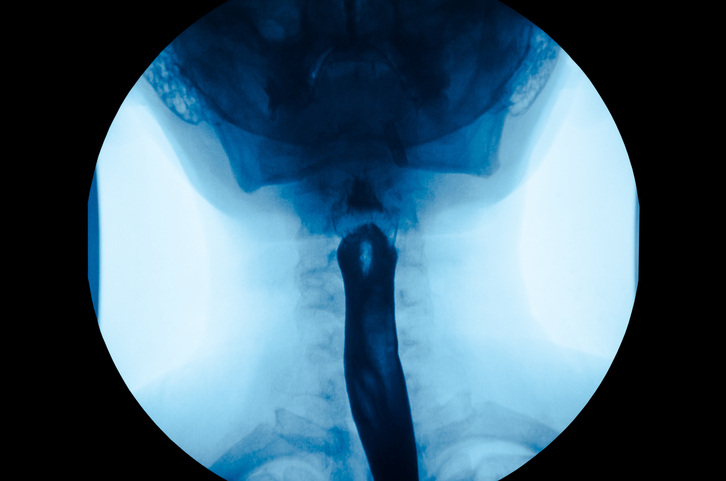

Le varici esofagee sono determinate da un'escrescenza di natura vascolare nell'ultimo tratto dell'esofago, se non a livello del cardias: la valvola che regola il passaggio di cibo dall'esofago allo stomaco.

COSA SONO E COME SI TRATTANO LE VARICI ESOFAGEE?